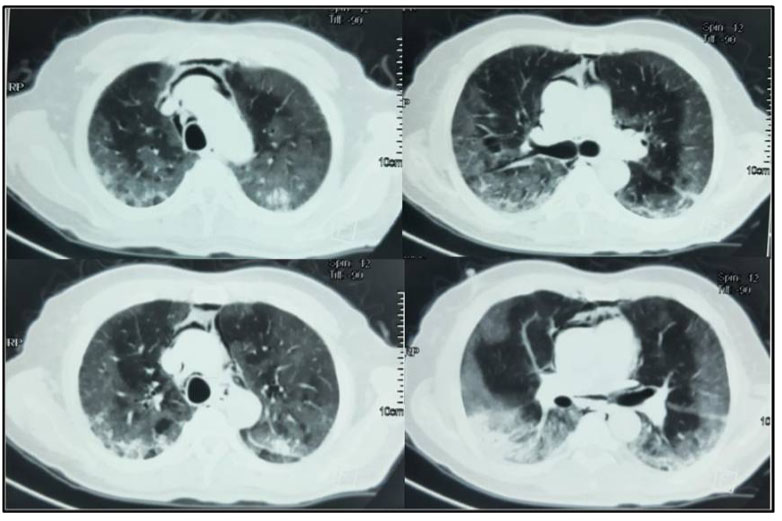

A 50-year-old female patient with past history of obesity with BMI at 30 kg/m2 was admitted in our ICU for acute respiratory failure due to COVID-19 pneumonia. There was a history of dyspnea asthenia and cough one week before ICU admission. The patient was initially managed in the pulmonology department with non-rebreather oxygen mask. A non-contrast chest CT scan was performed showing diffuse bilateral ground-glass opacities with posterior and peripheral predominance associated to alveolar consolidation with estimated percentage of lesion at 75% consistent with severe COVID-19 pneumonia (Figure 4A). In front of worsening of his respiratory state, she was transferred to our ICU with moderate acute respiratory failure. Upon admission, her respiratory rate was of 40 breaths/min with struggle signs, SpO2 of 88% under 15 L/min of oxygen with non-rebreather mask, she was conscious with stable hemodynamic state. Blood test results showed a CRP of 81 mg/L, leukocytes of 18.400/mm3, D-dimer of 290 µg/L and the ABG showed respiratory alkalosis with pH: 7.47, PaO2: 51 mmHg, PaCO2: 32 mmHg, HCO3−: 23 mmol/L, and SaO2: 88%. The patient was put initially under NIV (PS of 20 cmH2O, PEEP of 6 cmH2O, and FiO2 100%); antibiotics, dexamethasone 6 mg/12 h, anticoagulation and prone positioning. At day 6 of ICU stay she was intubated in front of NIV failure using direct laryngoscopy with no difficult airway management, no bougie or stylet were used and 7.5 cm tracheal tube was inserted at level 23 of dental arch. The patient was ventilated with protective ventilation with VAC mode (Vt: 6 mL/kg of PBW, PEEP: 10 cmH2O, RR: 26 breaths/min, and FiO2 100%). Under protective ventilation, peak airway pressure (PIC) was of 28 cmH2O, plateau pressure (P.Plat) of 24 cmH2O, and driving pressure (DP) of 14 cmH2O. She was immediately put under continuous infusion of sedation and neuromuscular blockers. Four hours after intubation a subcutaneous emphysema appeared in the neck, chest wall, and in the abdomen. On examination there was a symmetric crackle on thoracic auscultation without silence, respiratory mechanics showed increasing in PIC of 35 cmH2O and P.Plat of 30 cmH2O without worsening of hemodynamic state. A non-contrast chest CT scan was performed showing: huge PM reaching the right peritoneal space associated with an important subcutaneous emphysema in the neck and thoraco-abdominal region with suspected tracheal perforation with worsening of the ground-glass opacities and inferior alveolar consolidation, no pneumothorax was associated (Figure 4B). In front of the deep hypoxemia (PaO2/FiO2 of 80 and SpO2 at 86% with deep decrease of SpO2 till 50% while ventilator disconnection attempts), a flexible bronchoscopy to identify the tracheal breach wasn't possible. The attitude was to introduce the tracheal tube till 27 level of dental arch to plug the tracheal breach with the balloon (according to the CT thoracic scan data we recommend us to introduce the tracheal tube by 4 cm approximately), decreasing the PEEP to 6 cmH2O with close monitoring of the hemodynamic and respiratory state. The evolution was marked by the regression of the subcutaneous emphysema five days later and the improving of the respiratory state (PaO2/FiO2 of 200, SpO2 at 95% and peak pressure of 28 cmH2O). A non-contrast chest CT control scan was performed showing a significant regression of the PM and the subcutaneous emphysema with persistent severe lung lesion with ground-glass opacities and consolidation images (Figure 5). The patient was maintained under protective ventilation with difficult weaning. The evolution was marked by a septic shock due to ventilator acquired pneumonia, and she passed away at day 18 of ICU stay in a refractory shock.

Figure 4: (A) Non-contrast chest CT scan showing diffuse bilateral ground-glass opacities with posterior and peripheral predominance associated to alveolar consolidation with estimated percentage of lesion at 75% consistent with severe COVID-19 pneumonia. (B) Chest CT scan showing bilateral ground-glass opacities and alveolar consolidation along with huge pneumomediastinum (yellow arrow) and subcutaneous emphysema (blue arrows).